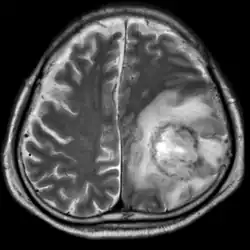

![]() | |

| T2-weighted MRI showing a necrotic brain abscess caused by Acanthamoeba. | |